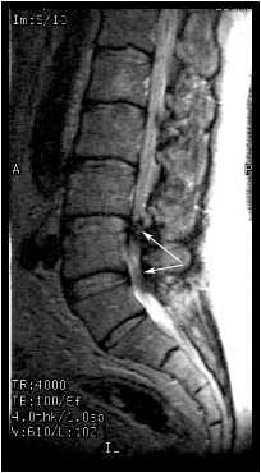

Стенозом позвоночного канала называют уменьшение его размера в передне-заднем направлении, а также уменьшение его ширины. Сужение позвоночного канала в поясничном отделе наиболее часто встречается при гипертрофии (увеличении) фасеточных суставов, желтой связки, уменьшении фораминального отверстия (места выхода нервного корешка из позвоночного канала) за счет разрастания остеофитов, изменении оси позвоночника (сколиоз, спондилолистез). (Рис.1,2А,В)

Немного анатомии. Позвоночный канал спереди образован телами позвонков и межпозвонковыми дисками, сзади дужками позвонков, между которыми находится плотная желтая связка, с боков – фасеточными суставами. В позвоночном канале находится спинной мозг с выходящими из него спинномозговыми корешками, окруженный соединительнотканной оболочкой: т.н. твердой мозговой оболочкой образующей дуральный мешок. (Рис.3,4,5).